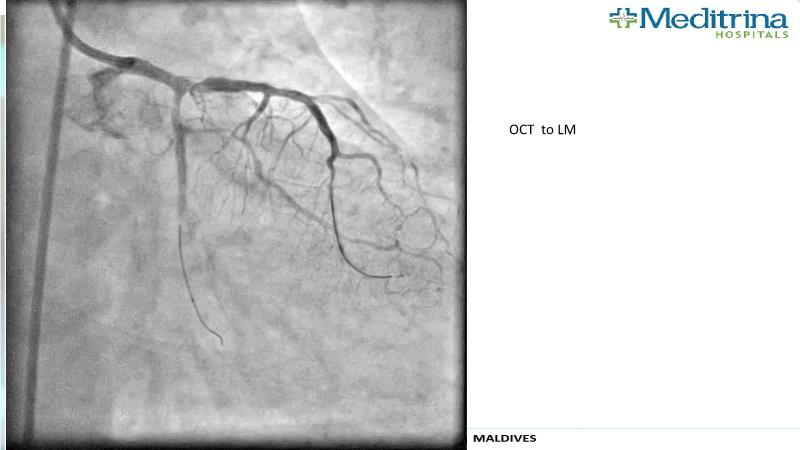

- To define the use of OCT in PCI of complex coronary lesions